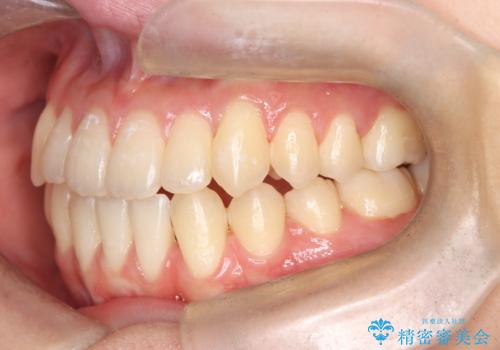

転院という不安な状況にある患者様のストレスを最小限に抑えつつ、歯の健康を最優先にした処置を行いました。

装置の変更と歯肉への配慮: ワイヤー矯正は歯の根(歯根)を平行に移動させる「歯体移動」を得意としています。本症例では、歯肉退縮を防ぐために、歯の傾きを精密にコントロールしながら抜歯スペースを閉じる必要がありました。ワイヤー装置を用いることで、インビザラインでは難しくなっていた三次元的な細かい調整を可能にしました。